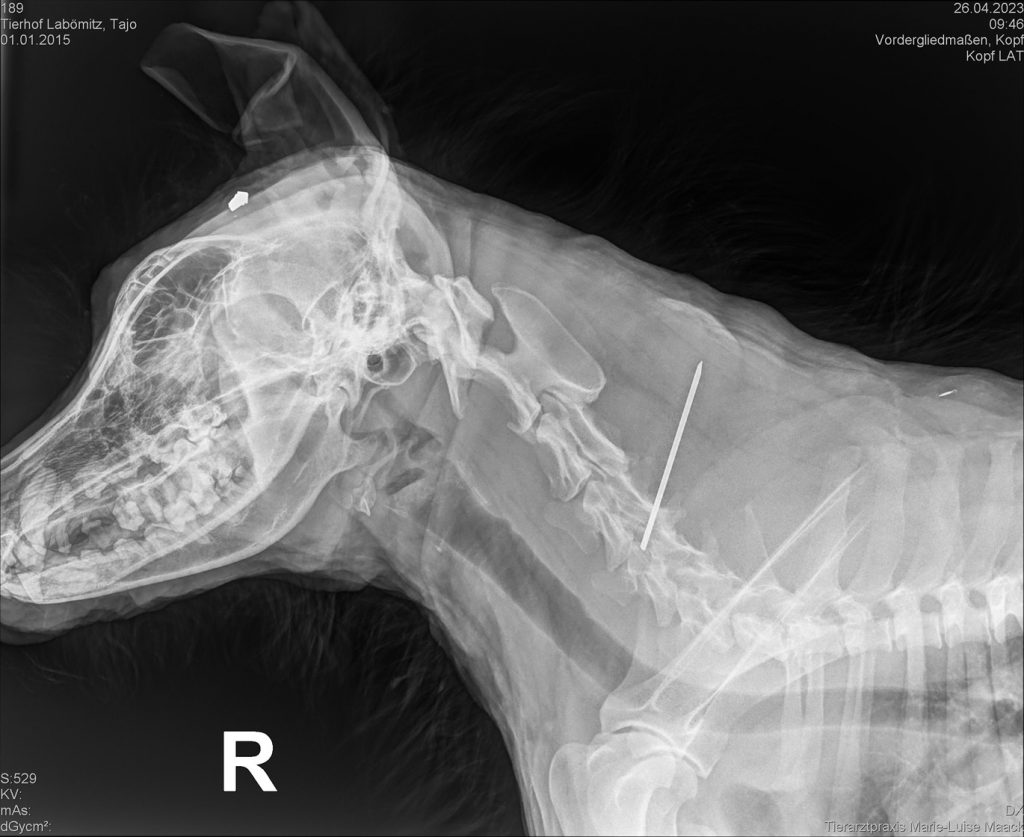

Unsere Tierarztpraxis Marie-Luise Maack röntge heute unseren Rumänen Taio. Der gemütliche Kuschelbär humpelt bekanntlich und auch seine Schulter schien uns geschwollen.

Luise und Franzi waren erstaunt, mit welcher Ruhe und Gelassenheit Taio das mobile Röntgen über sich ergehen lies. Das Ergebnis war dann nicht so schön. Taio hat eine vermutlich einmal gebrochene Pfote, die schlecht oder gar nicht operiert wurde. Dazu kommt eine Arthrose sowie ein Diabolo (Geschoss eines Luftdruckgewehrs) unter der Kopfhaut. Auch der undefinierbare Metallstab in der Schulter/Wirbelsäule gehört dort eigentlich nicht hin. Unsere Tierärztin wird sich noch ein zweite Meinung einholen und wir schauen dann gemeinsam, wie es weitergeht. „Und wenn sich keiner für Taio findet, bleibt er eben bei uns und wird Hofhund“, so Conny. Wir BEDANKEN uns bei Luise und Franziska und sind gespannt, wie es weitergeht.

Nach Analyse der Röntgenbilder wurde klar, das Taio für eine Versteifung des Vorderlaufes (er knickt bei Belastung immer schmerzhaft weg) zu wenig Knochenmasse vorhanden ist. Der Kirschner-Draht, der nach dem Bruch zur Stabilisierung eingesetzt worden war, ist inzwischen in die Schulter gewandert. Eine Versteifung des Gelenkes ist möglich, aber die Erfolgsaussichten sehr gering. Nach Abwägung aller Fakten entschlossen wir uns in Abstimmung mit Frau Dr. Quandt zur Amputation. Dabei werden der Draht und das Diabolo ebenfalls operativ entfernt. Damit kann Taio noch viele Jahre glücklich leben, wie groß seine Lebensfreude ist, zeigt das Video

Conny begleitete Taio nach Greifswald zur Tierarztpraxis Quandt und Bracke und durfte bei der fast 2stündigen OP dabei sein. Dabei wurde ihm auch der Kürschnerdraht der ersten OP entfernt, der mittlerweile gewandert war und auch Schmerzen verursacht haben muss. Und auch das Diabolo in seinem Kopf. Der tapfere, große Kämpfer stand bereits 1h nach der OP wieder auf seinen 3 Beinen. Noch sehr wackelig, aber er stand. Zuhause angekommen, sollte er sich eigentlich auf seinen Platz vor dem Kamin niederlassen, aber er bewacht schon wieder die kleine Mana in ihrem Kinderwagen.